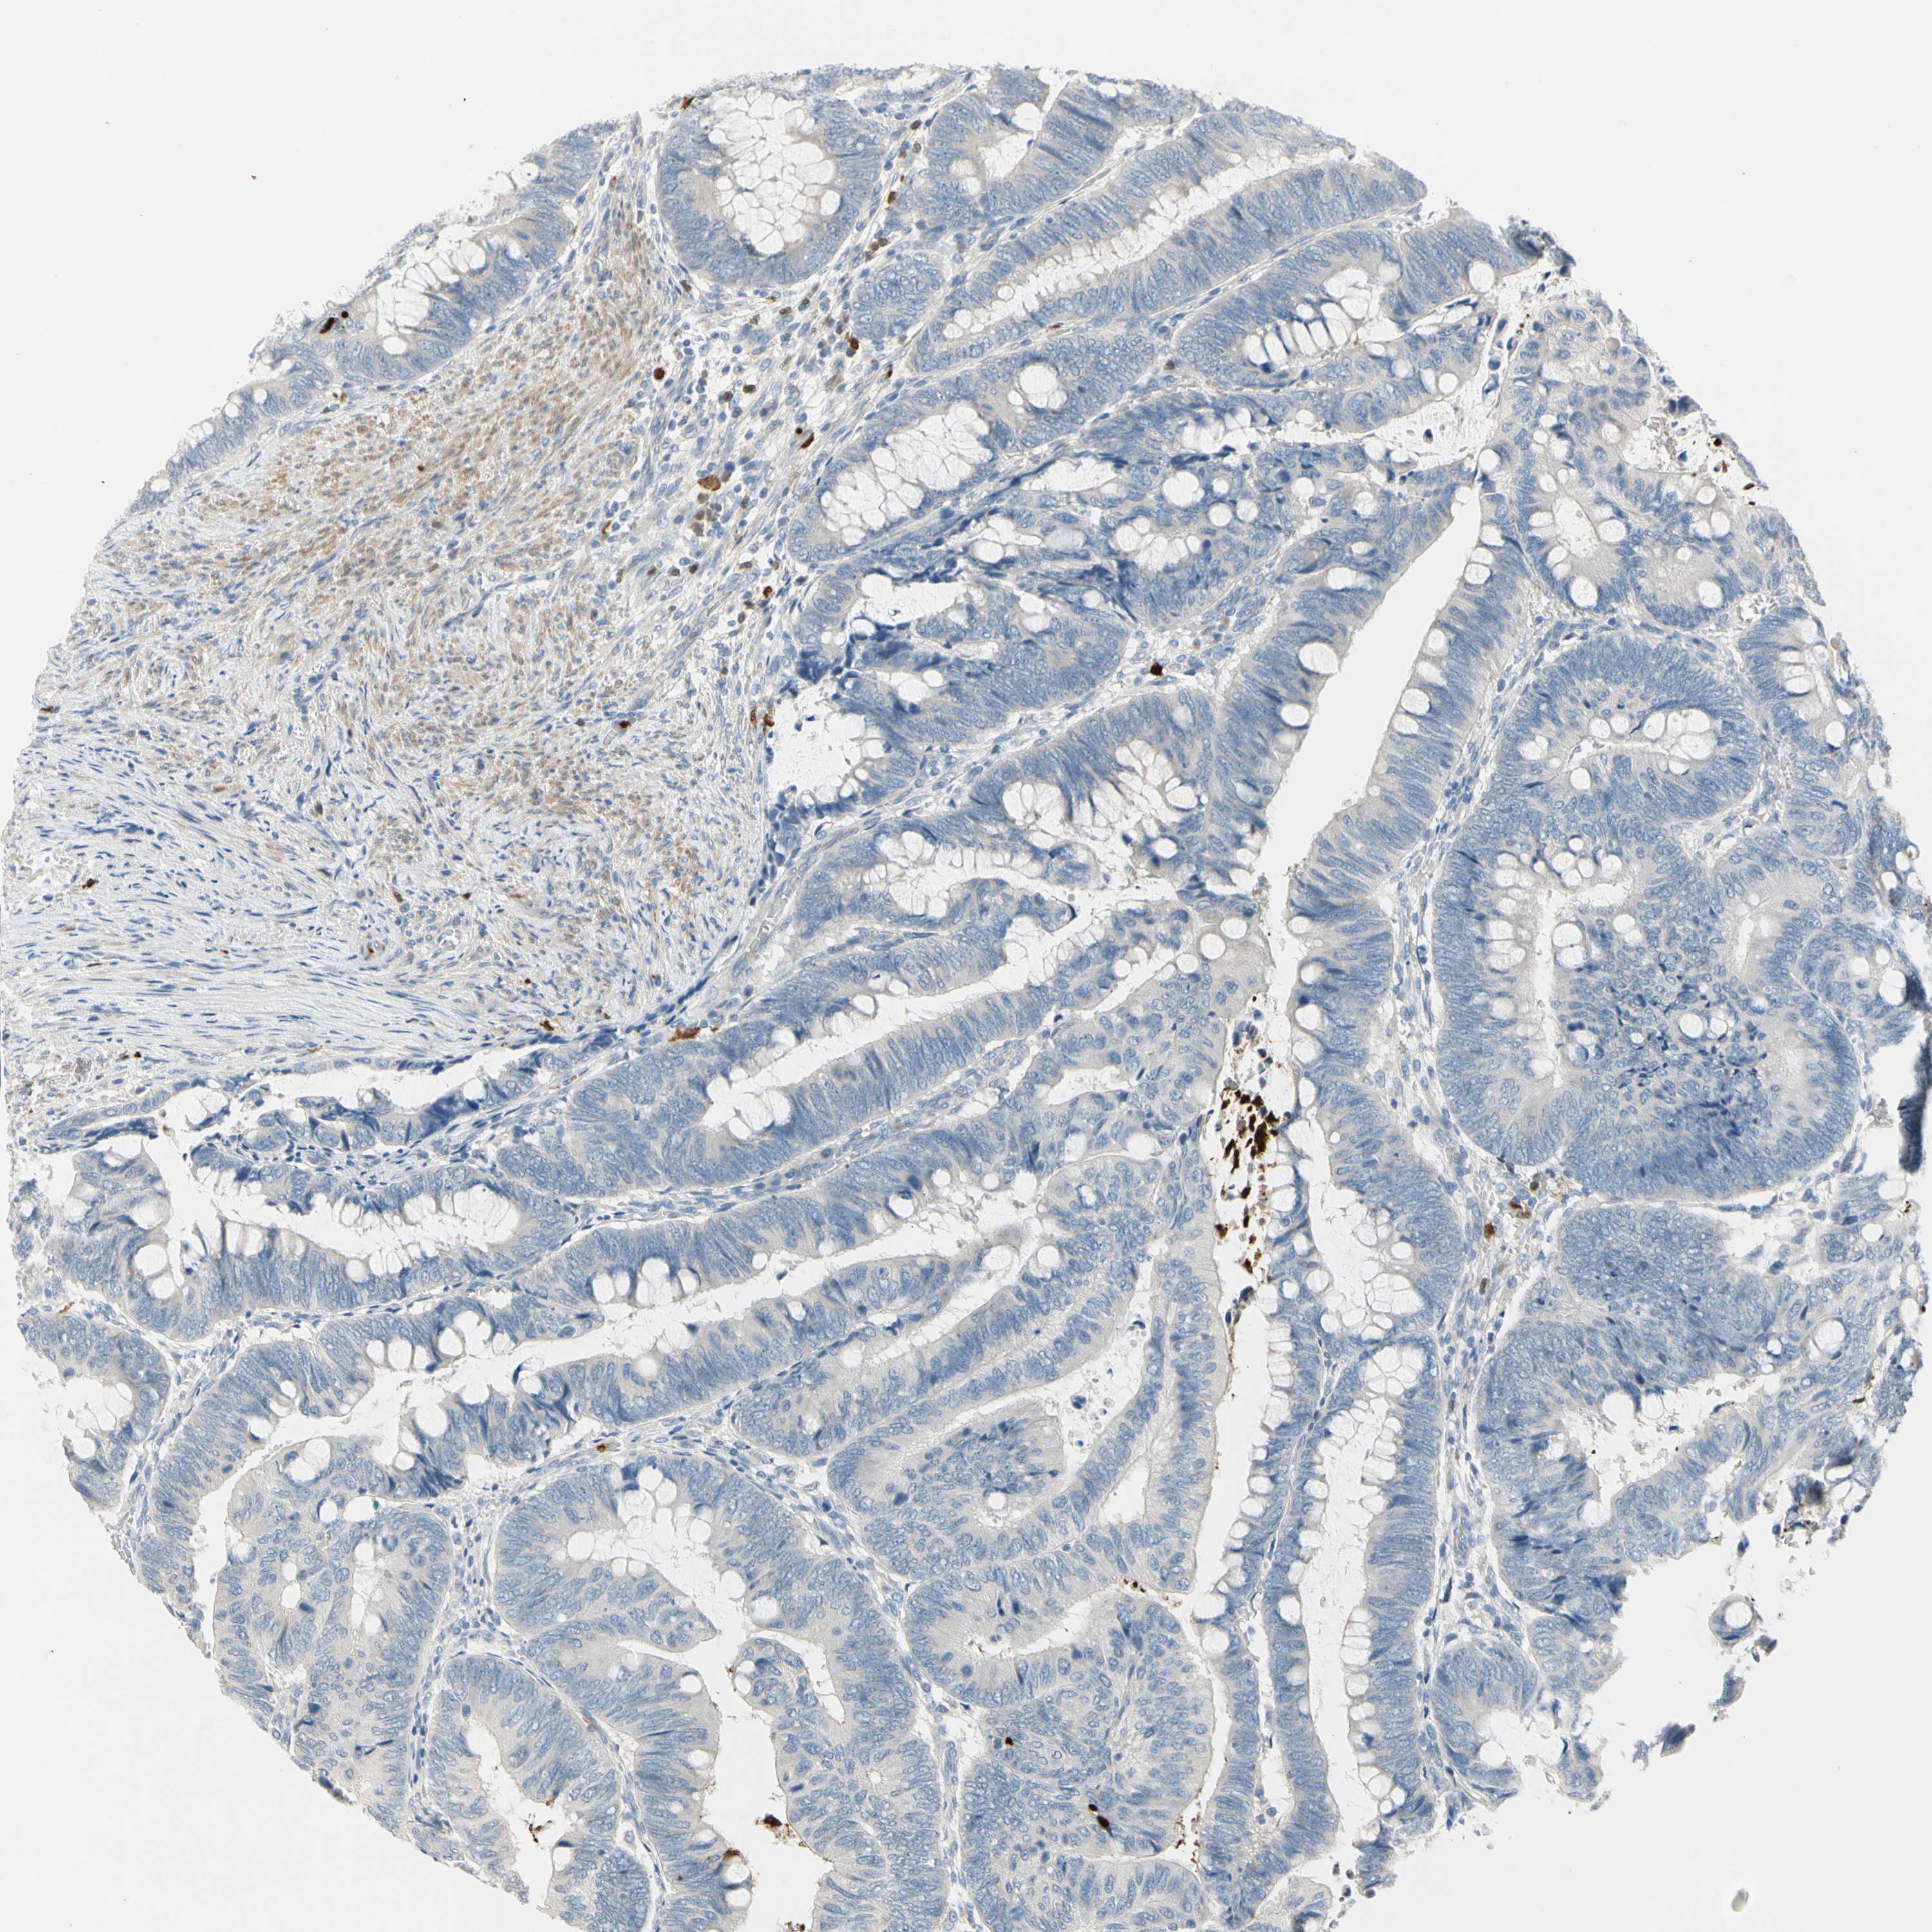

CANCER COLORECTAL CANCER Show tissue menu

Colorectal cancer

Human cancer

Colon adenocarcinoma